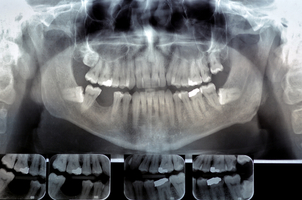

En la primera cita con el ortodoncista, se realiza un primer diagnóstico sobre el estado de los dientes. Para ello se harán exámenes como los siguientes:

En primer lugar el ortodoncista solicita una radiografía al paciente para evaluar el caso y realizar el molde. En ocasiones es necesario un tratamiento previo como la extracción de algunas piezas dentales.